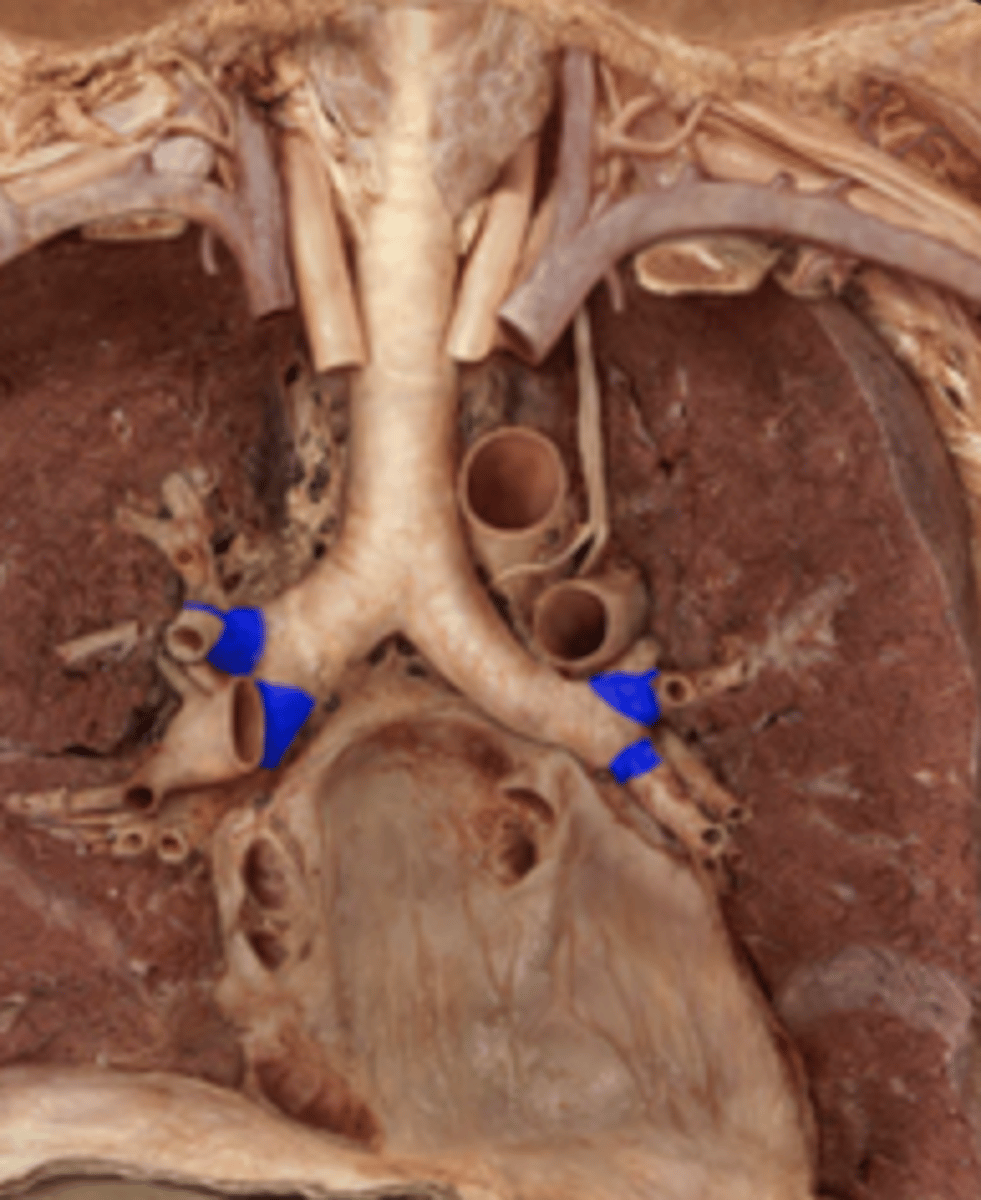

Carina

Right Primary Bronchus

Left Primary Bronchus

Secondary Bronchus

Tertiary Bronchus